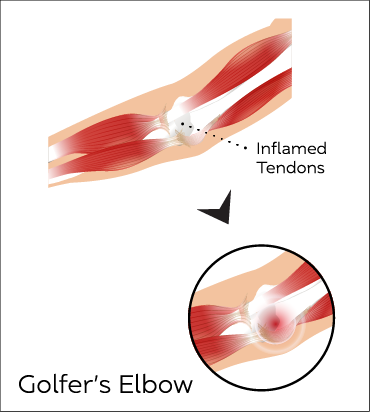

Golfer's elbow

Golfer’s Elbow is a condition that causes pain and inflammation in the tendons connecting the forearm to the elbow.

Golfer’s Elbow is common in people who go from rarely using their forearm muscles to using them a lot.

The most common signs of Golfer’s Elbow are pain and tenderness on the inner side of the elbow that can extend along the forearm, a general stiffness of the elbow, weakness in the wrists and hands and a possible numbing sensation or tingling in the joint.

Ultrasound can be used to identify and confirm the condition. An ultrasound guided injection using steroids, hyaluronic acid or regenerative medicine products can be offered as treatment.